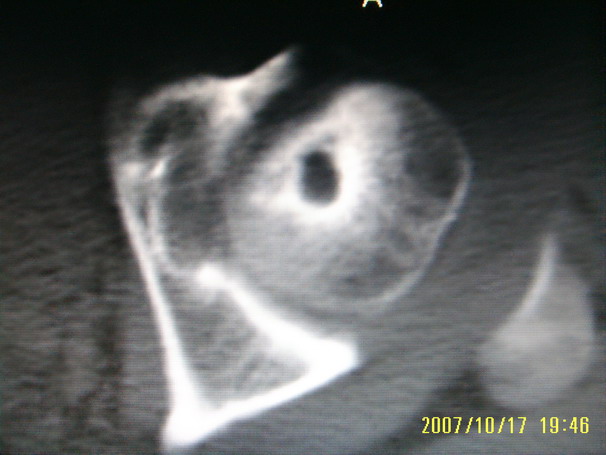

标题: CT10352:女,45岁,股骨头病变,如何诊断? [打印本页]

标题: CT10352:女,45岁,股骨头病变,如何诊断?

股骨头病变,如何诊断?

患者女,45岁,左髋部行走疼痛一年,无外伤史,无感染史。x片示囊状骨透亮区

左侧股骨头变形,密度增高,局部塌陷。多考虑:股骨头缺血性坏死伴退变!

左侧股骨头塌陷,其内囊变硬化,骨纹理改变考虑:左侧股骨头坏死及蜕变.

股骨头形态尚可,骨皮质环厚度及完整性可,病灶区以外骨质尚未见明显异常,临近髋臼骨质亦可见类似改变,考虑退变性关节面下囊变可能性大,骨样骨瘤等不排除,

股骨头形态尚可,骨皮质环厚度及完整性可,病灶区以外骨质尚未见明显异常,临近髋臼骨质亦可见类似改变,考虑1.动脉瘤样骨囊肿,2.股骨头缺血坏死,

股骨头形态尚可,骨皮质环厚度及完整性可,病灶区以外骨质尚未见明显异常,临近髋臼骨质亦可见类似改变,考虑退变性关节面下囊变可能性大

双侧股骨头形态都欠规整,外形欠光滑,尤以左侧明显,考虑双侧髋臼发育不良并退行性变